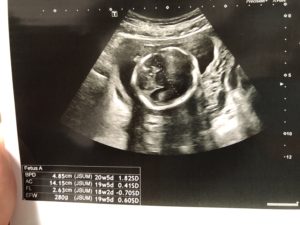

妊婦健診に4週間ぶりに行きました。

血圧、尿検査、体重は問題なし。

今日は子宮頸管長も測定し、正常。

前回検査した採血結果も異常なし。

でも先生に「ちょっと胎盤の位置が低いね。治る場合もあるけど、このままだと帝王切開で産む事になるね」と。

まるちゃんの方は元気にしていました。

頭が大きそう…

お腹の上も下も胎動が活発にあって、もしかして逆子⁇と心配してましたが、大丈夫でした。